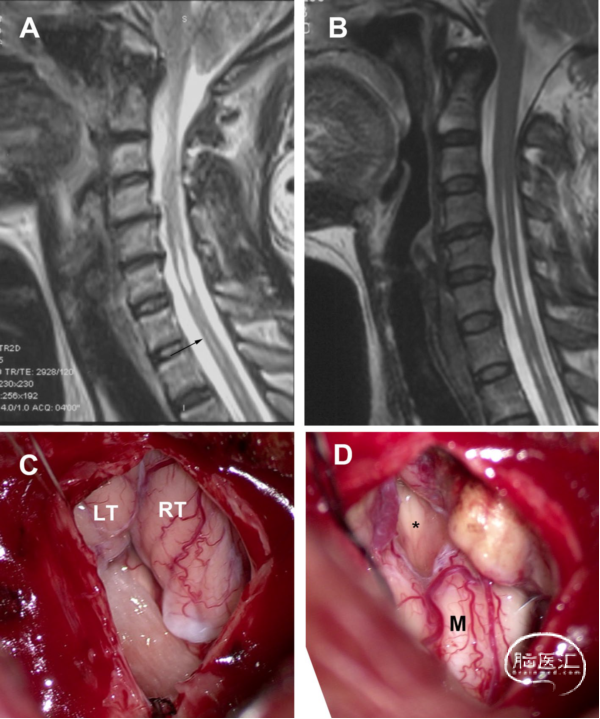

男性,29岁,有10年头痛和颈部疼痛病史。术前MRI显示,SM延伸至C1水平的下缘,不与第四脑室相通。术中见,扁桃体居中,占据枕骨大孔,并覆盖Magendie孔。进行软膜下扁桃体切除术。术后MRI显示,SM的大小明显缩小。术后症状部分缓解(图4)。

图4. 非交通型CM-SM病例。A. 术前MRI-T2矢状位加权成像。SM向上延伸至C1的下缘。B. 高分辨率MRI显示,SM的上端与第四脑室不连通。C. 术后MRI显示SM明显减少。D. 硬膜切开后,显示中间化的扁桃体占据枕骨大孔和覆盖Magendie孔。E. 显露Magendie孔,脑脊液在其中自由流动(星号)。F. 进行软膜下扁桃体切除术,可以看到Magendie孔(星号)。